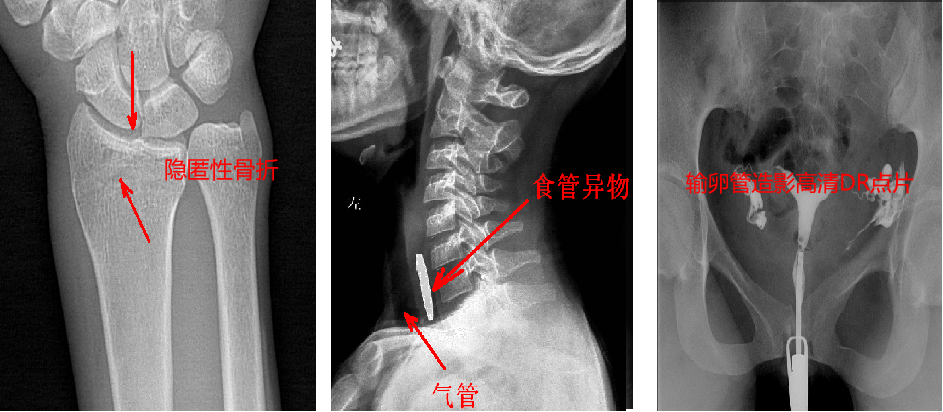

靜態(tài)DR最大的缺陷來自于盲拍,因此造成誤診發(fā)生率高,是保證診斷準(zhǔn)確性的巨大阻礙因素。在靜態(tài)拍片中,部分特殊病灶容易被遮掩而導(dǎo)致漏診,在一些特殊造影上需要憑借醫(yī)生的臨床經(jīng)驗(yàn)才能獲取有效影像。而動(dòng)態(tài)DR依靠可視化高速高清點(diǎn)片功能,改變了傳統(tǒng)的盲拍模式。動(dòng)態(tài)DR在低劑量數(shù)字透視的情況下,能夠進(jìn)行疑似病灶部位點(diǎn)片,極速精準(zhǔn)獲取有效信息,同時(shí)可即時(shí)回放視頻信息,在臨床上極大地提高了病變的檢出率,降低漏診誤診。

與此同時(shí),動(dòng)態(tài)DR的成像視野與精度也勝于靜態(tài)DR。動(dòng)態(tài) DR17×17 英寸方形幅面進(jìn)行動(dòng)態(tài)成像,能夠?qū)鹘y(tǒng)動(dòng)態(tài)造影幅面小的問題全部解決,同時(shí)由于幅面較大,臨床操作技師能夠在一個(gè)大的幅面下觀察診斷,當(dāng)看到病變部位時(shí)實(shí)時(shí)高清點(diǎn)片,從而很好地捕捉到病變點(diǎn),也大大降低了檢查時(shí)間。